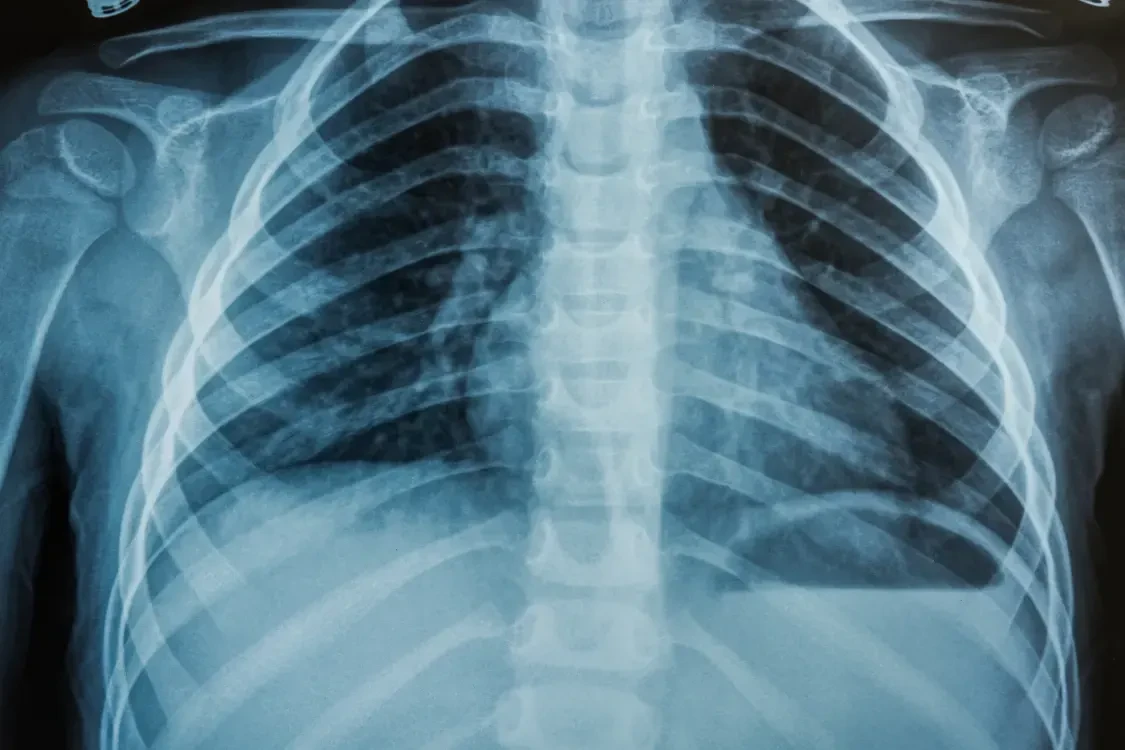

A doctor can confirm pneumonia by listening to the lungs and taking a chest xray. With appropriate antibiotics and medical care, pneumonia is treatable, especially when identified early. Seek prompt medical help if these pneumonia symptoms arise.

- Chest x-ray to visualize lung infection.